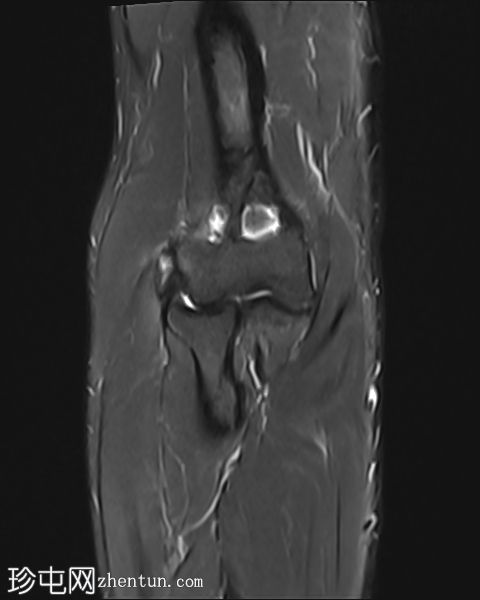

冠状位

T1加权像

STIR序列

肘关节伸肌总腱增厚,腱内可见高信号及部分撕裂。伴周围软组织水肿。

本病例展现了网球肘的典型

影像

学特征。